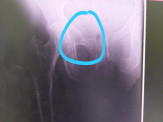

O neto do casal idoso Dyonnatan (que é Bombeiro Militar) foi até a residência e conduziu sua avó até a uma UPA por volta das 16:40h da terça-feira (14), onde foram realizados alguns Raio-X e constatou-se duas fraturas na bacia da idosa Clarice.

A mesma continuou na UPA até o fim da manhã de hoje (16), onde foi transladada para a unidade médica da Santa Casa, onde possivelmente será operada.